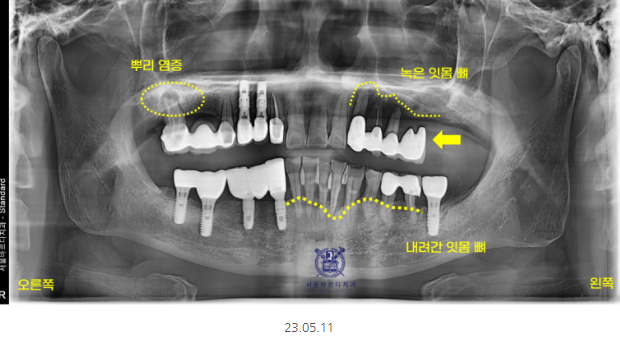

처음 내원 시 사진입니다.

전반적으로 풍치가 진행되셨네요~

그만큼 전반적으로 잇몸뼈가 내려가

흔들리는 것으로 안좋다는 것입니다.

왼쪽 위가 불편하신 게 가장 크다고 하셨는데요.

좀 특이한 모양이죠~?

맨 끝 치아가 머리만 둥둥 떠있네요.

예전에 많이 쓰이던 치료법으로

캔틸레버 브릿지라 불립니다.

한쪽만 지지된 채로 다른 끝은 공중에 떠있는 형태를 뜻해요.

이러다 보니 허공에 떠 있는 치아의 힘까지

앞쪽 치아가 받게 되어서

무리를 주게 됩니다.

오랜 시간 이런 힘이 축적이 되면

멀쩡했던 앞쪽 치아들까지 상하게 되는데요.

힘이 누적해서 가해져서

잇몸 속의 뼈와 치아의 뿌리도 계속해서 손상되게 되는데요.

그래서 사진을 보시면 앞쪽 치아 뿌리가 드러났죠~?

잇몸뼈가 내려가서 그런건데

바로 손상되었다는 증겁니다!!!

x-ray 상에서 까맣게 보이는 부분이

뼈가 녹은 부분입니다.